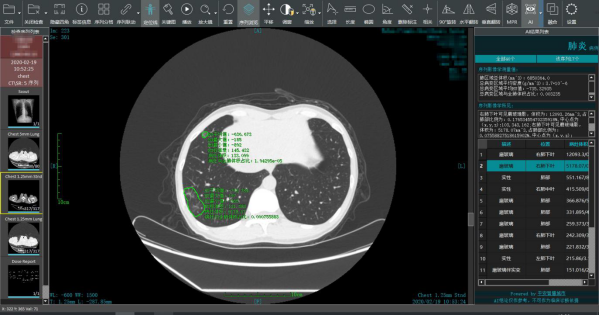

图片说明:平安智慧城市智慧医疗新冠肺炎智能阅片系统为疫区一线进行智能阅片,出具智能分析结果

平安智慧城市联席总经理兼首席战略官高孟轩介绍,平安智慧医疗新冠肺炎智能阅片系统一方面可以提升一线放射科医生的效率,15秒左右就能出具智能分析结果,准确率高达90%以上,对同一患者不同次扫描图像进行对比分析,可以让影像科医生在阅片过程中掌握更多病灶信息,出具更权威精准的CT诊断报告。另一方面,面对CT阅片量猛增、疫区一线放射科医生短缺的情况,平安智慧医疗新冠肺炎智能阅片系统可以通过远程AI阅片的方式支援。

众所周知,核酸检测作为病原学证据被公认为新冠肺炎诊断的主要参考标准,但在国家卫健委历次《新型冠状病毒感染的肺炎诊疗方案》的各试行版中,符合新冠肺炎影像学特征的病例被定义为“疑似病例”。一位疑似病人肺部CT大约有300多幅图像,阅片时间在15分钟左右。特别是“肺部影像学显示24-48小时内有病灶明显进展>50%者按重型管理”,对影像科医生对比多次影像的要求进一步提高。